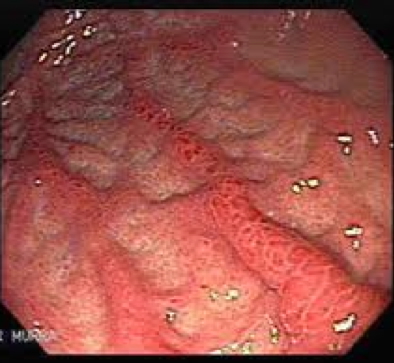

- Endoscopy + gastric biopsy – assess inflammation, test for H. pylori, rule out malignancy